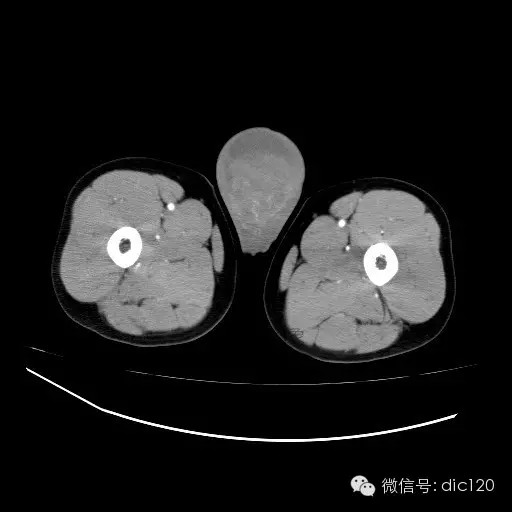

青年男性,右侧睾丸肿大,边界清晰,增强后睾丸不均匀中度强化,内可见多灶囊变坏死区,动脉期肿块内有细小动脉血管显示,延迟期可见分隔样强化,鞘膜囊可见积液。

定位定性:右侧睾丸恶性肿瘤。

【影像诊断】

右侧睾丸精原细胞瘤,右侧睾丸鞘膜积液。